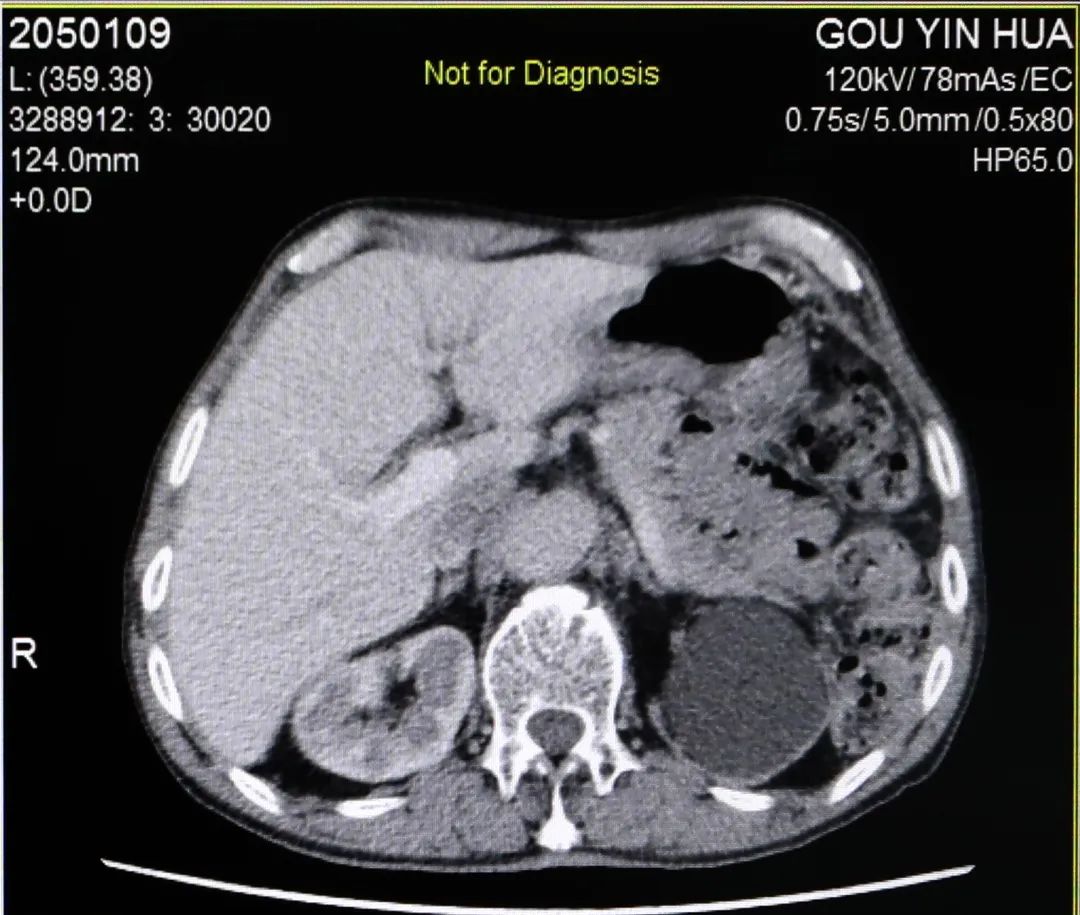

X光拍片显示杨大爷左侧输尿管有一2cmX1.2cm大小结石光影,在接下来的B超检查和增强CT检查中发现,杨大爷那颗卡在左侧输尿管的结石已经导致左肾萎缩失去了功能。 B超检查 CT检查 泌尿外科主任齐正华将检查结果告知杨大爷,提示他“左边的腰子保不住了,要切掉”。生性爽直幽默的杨大爷呵呵一笑:“既然没得用得了,割来甩了就是。” 心电图检查 在完善心电等术前相关检查后,10月27日上午,杨大爷被送进了手术室。泌尿外科主任齐正华和助手袁伟主治医师为杨大爷进行“腹腔镜下左侧无功能肾切除术+左肾周围粘连松解术”。 麻醉医师为手术提供保障 2个多小时全神贯注的手术 切除下的左肾 历时2小时40分,杨大爷萎缩无功能的左肾被成功取出,腹膜完整保留,整个过程出血量仅约10毫升。 泌尿外科主任医师杨胜云、主治医师袁伟检查杨大爷手术创口情况 经过几天的术后抗炎对症治疗,杨大爷尿量正常,各项指标无异常,于11月2日出院回家。 主治医师袁伟向杨大爷交待出院注意事项,杨大爷连连表示感谢。 专家提醒 泌尿外科主任、副主任医师齐正华提示:杨大爷本可保住这个肾的,由于早期结石形成的时候没有引起足够的重视,导致肾积水发生,积水时间一长就影响到肾功能,最终导致肾功衰肾萎缩。 齐正华说,临床上这类病例有很多,都跟杨大爷一样,早期往往仅出现腰胀腰痛等症状,因为还能耐受得住,所以大多数的患者都不会往尿路结石方面去想。 齐主任温馨提醒各位结石患者及朋友们,平时要多饮水,定期到正规医院进行健康检查,早发现,早治疗,别让“时间”成为了我们一辈子的遗憾。 泌尿外科专科门诊:新门诊综合楼二楼212诊室。 特需专家门诊:每周四上午,新门诊综合楼一楼113诊室。 泌尿外科住院部:住院综合大楼五楼。 咨询电话:0830-5266595